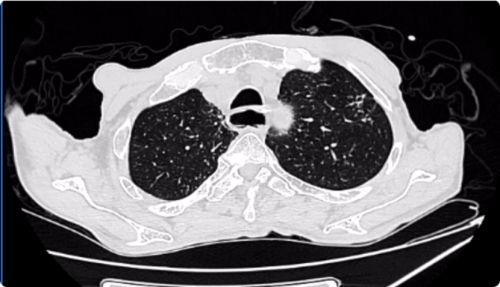

入院时CT: